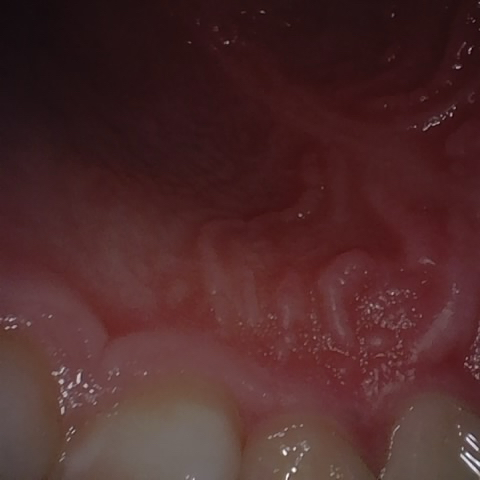

Image 1320 / 1535

NHD39990

Annotated as "Good"

Original Image Rendering Image